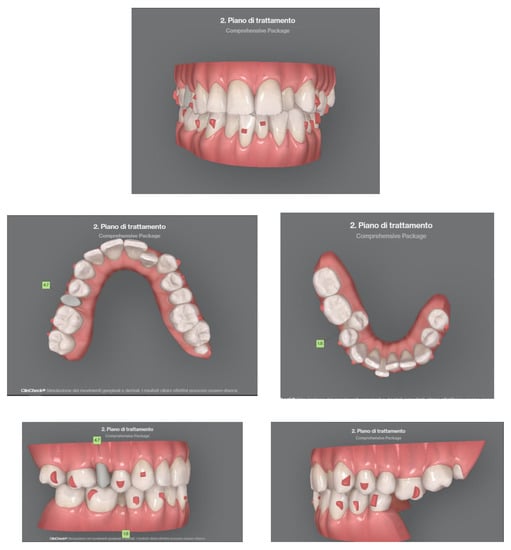

Case 2 concerns a 57-year-old male, with no systemic diseases. He came to our observation in November 2019, to carry out an orthodontic treatment to improve the esthetic appearance of his smile. He showed a good oral hygiene and periodontal condition. Intra-oral evaluation showed a reduction of the transverse diameters, both in the upper and lower dental arches, and a lack of space for the tooth 4.5 in the lower arch (Figure 9 and Figure 10). It was planned to re-establish elements 1.6 and 3.6 after orthodontic therapy in order to reach the first molar class. The most important problem for the patient was related to his smile esthetics and concerned the crossbite of the tooth 2.2.

His specific request was to obtain a noticeable improvement in his smile as soon as possible, with the resolution of the anterior crossbite. It was decided to use aligners to obtain esthetic and functional goals.

Figure 10. Clinical case treated with Invisalign© aligners. Intraoral views from ClinCheck. Frontal, upper, and lower occlusal and lateral view of occlusion before the beginning of treatment.